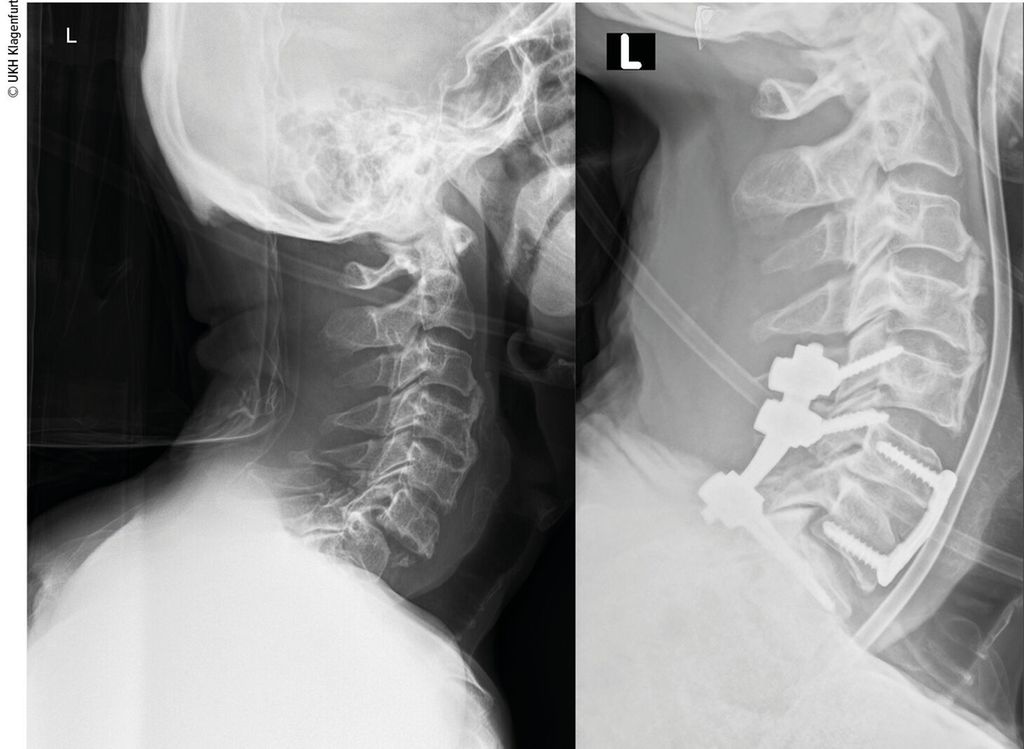

Typ-C-Verletzungen

Typ-C-Verletzungen werden meist kombiniert ventral und dorsal versorgt, da diese Versorgung biomechanisch die stabilste ist, vor allem am zervikothorakalen Übergang sollte eine 360-Grad-Versorgung angestrebt werden, um eine ausreichende Stabilität für die Fusion zu gewährleisten (Abb. 2).3